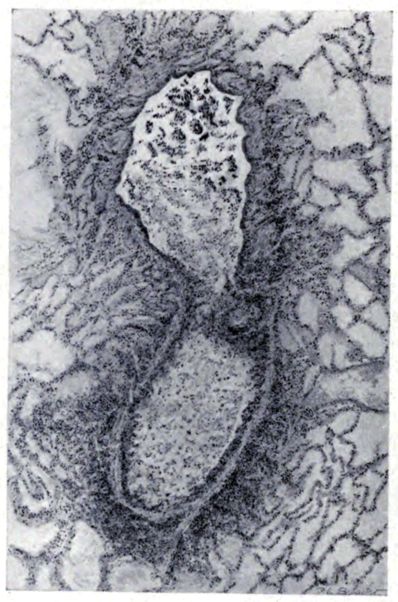

FIG. IV. AUTOPSY NO. 205. CONGESTION AND EDEMA OF THE SUBMUCOSA AND REGENERATION OF THE TRACHEAL EPITHELIUM.

The changes are less marked, perhaps, in the trachea than in its finer ramifications. The mucosa is constantly more or less destroyed and large areas, usually focal, are entirely devoid of their epithelial covering. This is replaced by a sparse exudate, composed largely of red blood cells, mucus, a small amount of fibrin, and nuclear fragments (Fig. II). It may dip into the submucosa for a short distance, but usually these indentures are associated with the ducts of the mucous glands into which the inflammatory reaction extends. A more striking feature than the exudate, however, is the edema and the congestion of the submucosa. The loose areolar tissue of the submucosa is spread widely apart, and throughout it distended blood vessels are very conspicuous. Occasionally such a vessel is broken and actual hemorrhage appears in the submucosa. Occasionally, too, the inflammation extends down the duct to the mucous gland itself, and here, also, aplastic inflammatory reaction is evident, inasmuch as the acini now stain intensely red with the cells undifferentiated from each other and specked here and there by broken remains of the dead nuclei (Fig. III). After the disease has continued for a short period, even at the end of five or six days, some regeneration of the epithelial lining may be seen (3) (Fig. IV). But despite this, the acute picture persists, and there goes on, side by side, an attempted repair characterized by epithelial regeneration and the same evidence of acute change. Since the lesion is essentially a superficial one, scars or contractures of any extent are not encountered in the trachea, even in examples of the disease that have ended fatally only after many weeks.[4]